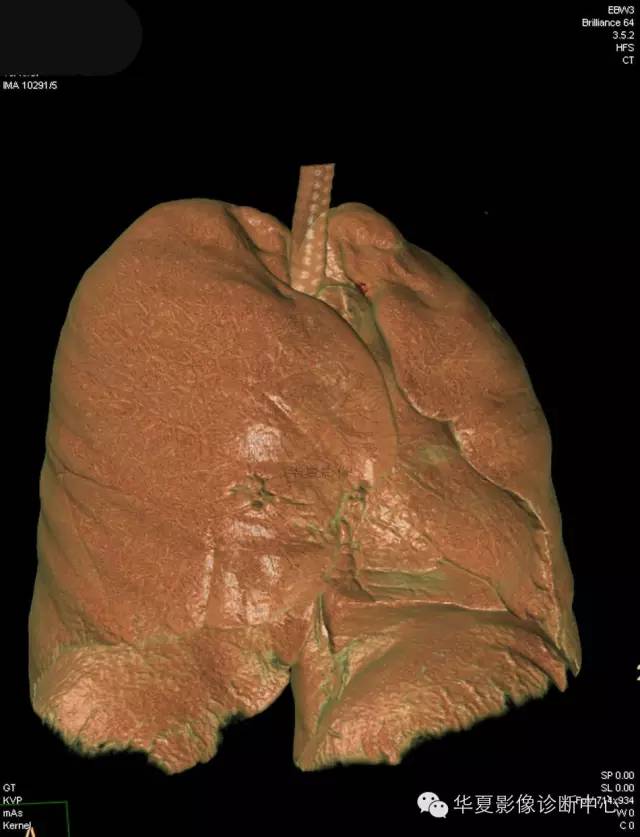

女,56岁,其父因肺癌去世,自觉胸部疼痛不适来诊要求拍胸片。

检查所见: